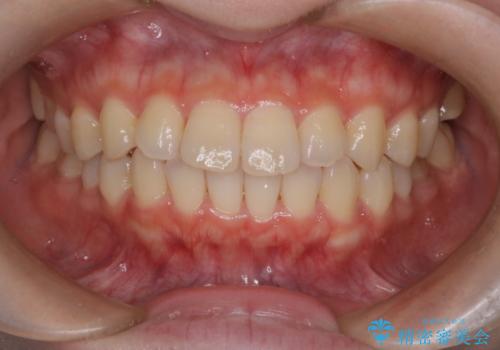

前歯と奥歯のガタガタを矯正で改善

担当医 河口智英